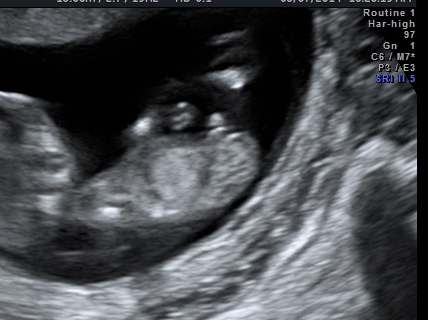

Thank u i cried when i first saw it but now that i look closer i feel like it could be 50/50! I feel terrible! I love this baby no matter what though =) I think the blob is the leg heres another pic.Attachment 17388Attachment 17388

i agree.. could be leg. it just seems too far back to be the nub. if it was the nub turning up, it seems (and from the 1000's of pics i've seen) that it would be more toward the end of the shaft part of the nub, and your blob is smack in the middle.

It's either a boy or there are no gender clues. The 2 lines are too far apart to be the nub and they don't start from the same place.

This is a picture of a straight up boy nub. See the ball with a gap under it? That's a boy bump. It's not leg or cord.

I personally don't think that's the nub, I saw your first post and that's a huge change in only a week. 1st scans were definitely girly. Looks to me like part of a leg going down and then the legs are crossed so nub wouldn't be seen. What did it look like during the actual scan?

Sorry if you are hoping to hear girl - if so, I hope I am wrong! but that looks like a perfect 13 week boy nub with the leg showing in behind. I don't think it looks unusually big, 13-14 weeks is when they big changes start becoming clear...

I also think it's too big for a nub, still going with girl